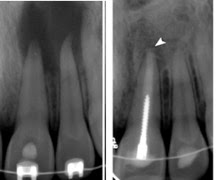

Το ακριβές μήκος του δοντιού, όπως και το μήκος εργασίας, το μετράει ο οδοντίατρος με ακτινογραφίες.

Αφού έχετε τελειώσει τη θεραπεία πρέπει να επισκέπτεστε κατά τακτά χρονικά διαστήματα, που ο οδοντίατρος θα σας ορίσει το ιατρείο για παρακολούθηση. Π.χ. σε περίπτωση ακρορριζικής βλάβης θα ελεγχθεί με ακτινογραφία η πορεία επούλωσης. Ενώ άλλες φορές μπορεί να κριθεί σκόπιμο να συμπληρωθεί η θεραπεία με ακρορριζεκτομή.